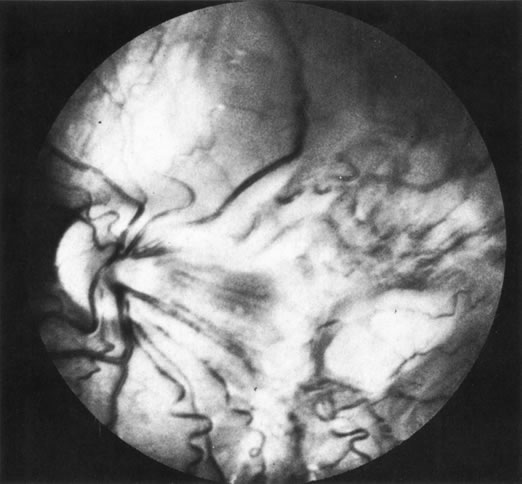

Combined retinal and retinal pigment epithelial hamartomas can also produce a pattern that simulates retinitis (Fig. 29). The pigment at the level of the retinal pigment epithelium, the surface fibrosis, and the vascular changes are typical features of this entity.

Fig. 29. Combined retinal pigment epithelial-retinal hamartoma. (Char DH: Clinical Ocular Oncology. 2nd ed. Philadelphia, Lippincott-Raven, 1996.)